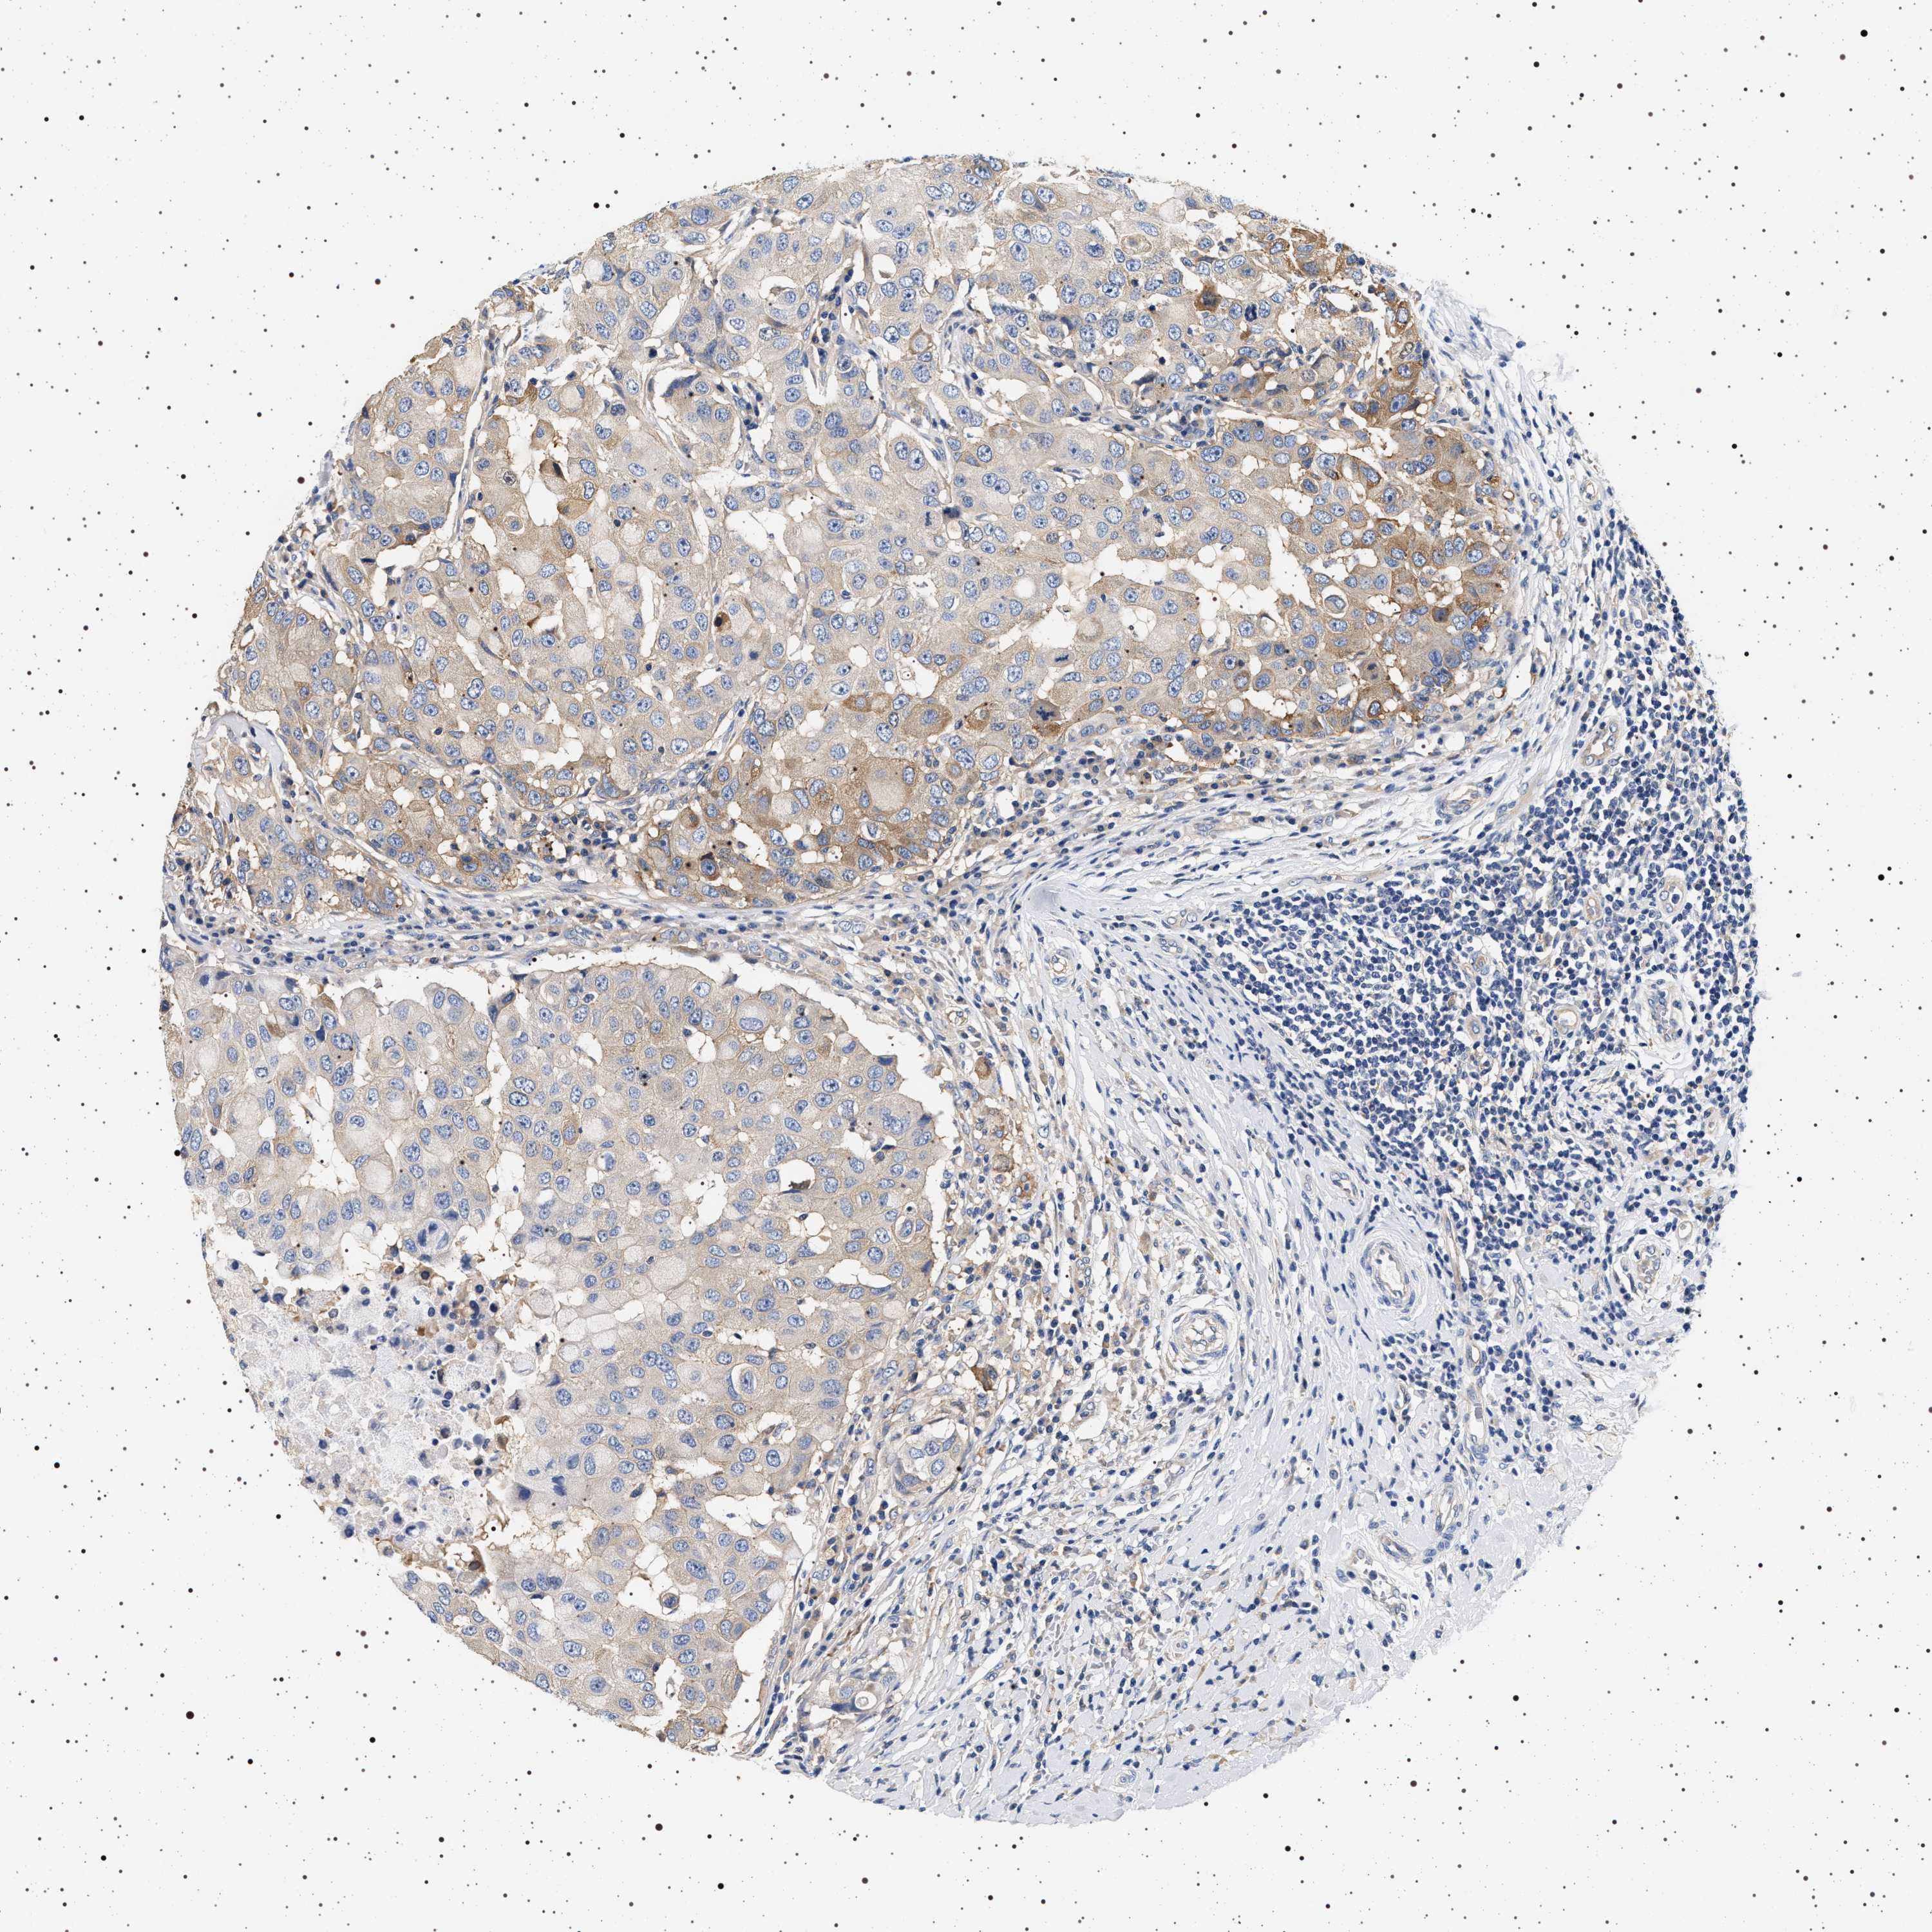

CANCER BREAST CANCER Show tissue menu

BRCA TCGA BRCA VALIDATION PROTEIN EXPRESSION

ANTIBODIES

AND

VALIDATION